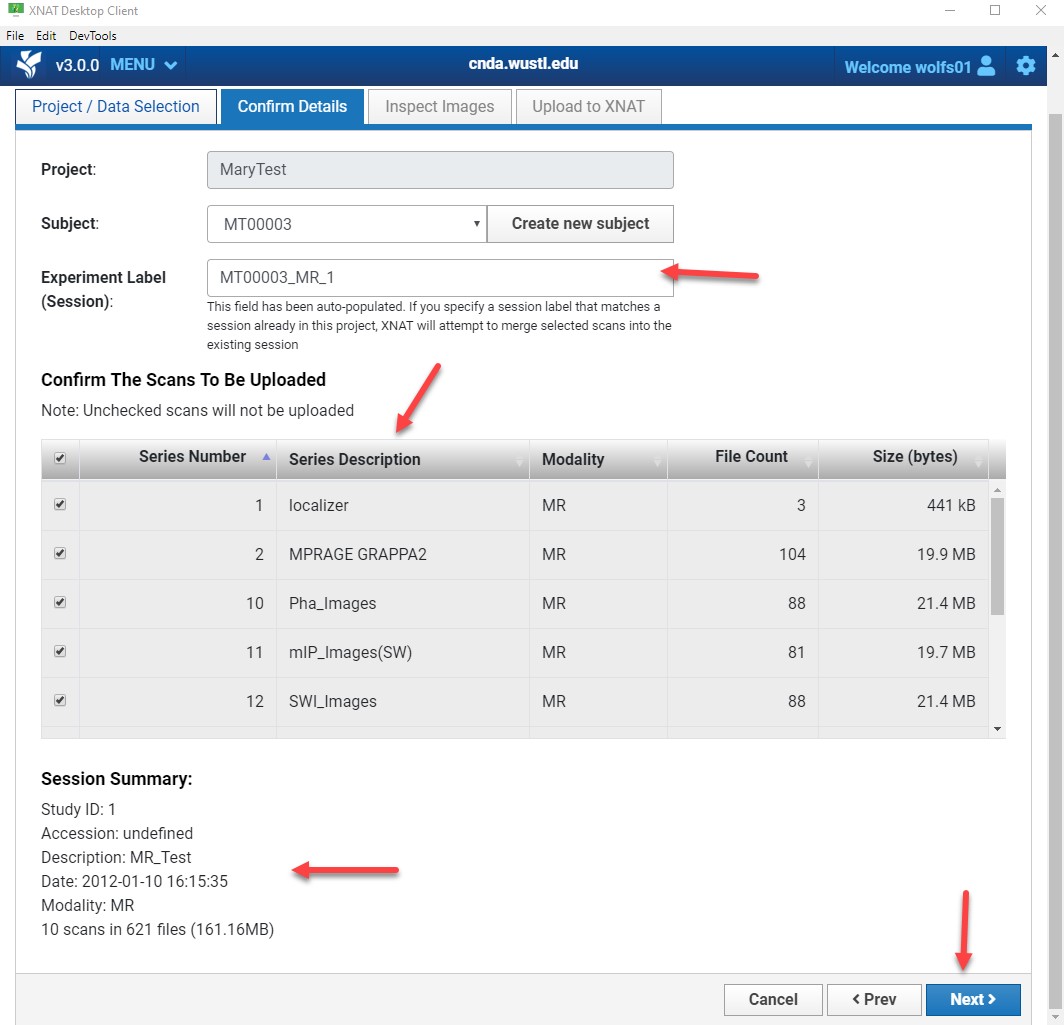

Session Label

The session label auto-fills. You may modify it if needed.

The session label must be unique within the project.

Review:

- Listed image series

- Session summary

Click Next.